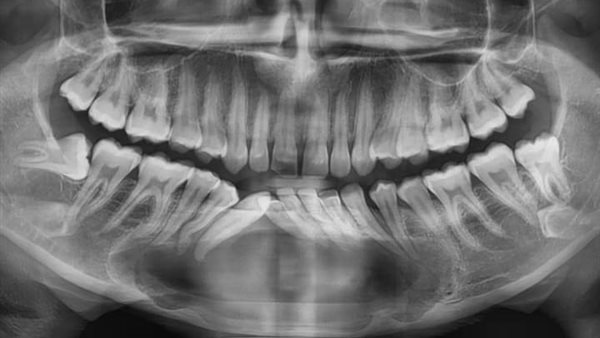

وقال الدكتور سمير حلاوة، إن حجم الكيس كان كبيرًا وممتدًا بعدة تكيسات من منتصف الفك السفلي إلى الجهتين اليمنى واليسرى، حتى منطقة النواجز (premolars)، مما تسبب في إزاحة جذور الأسنان المحيطة، وكان التحدي هو المحافظة على عظام الفك دون الاضطرار لاستئصالها وتعويضها بشريحة معدنية، والحفاظ على الأسنان والضروس المتأثرة.

وأضاف “كان التعاون بين فريق الجراحة وفريق حشو الجذور (حشو العصب)، الذي قام بحشو عصب جميع الأسنان المتأثرة والمحيطة بالكيس، وخلال فترة العلاج تم عمل تسريب وقتي للكيس لتقليل حجمه إلى أصغر صورة ممكنة مع تركيب دعامة أكريلك (obturator) للحفاظ على فتحة التسريب وإمكانية تنظيف وتطهير الفجوة لفترة امتدت أكثر من ستة أشهر، حتى تم استئصال الكيس بنجاح وتحليل أنسجته. وتم ملأ الفراغ العظمي بعظام صناعية مختلطة بعوامل نمو تحفيزية مشتقة من دماء المريضة نفسها تم إعداده داخل الوحدة”.